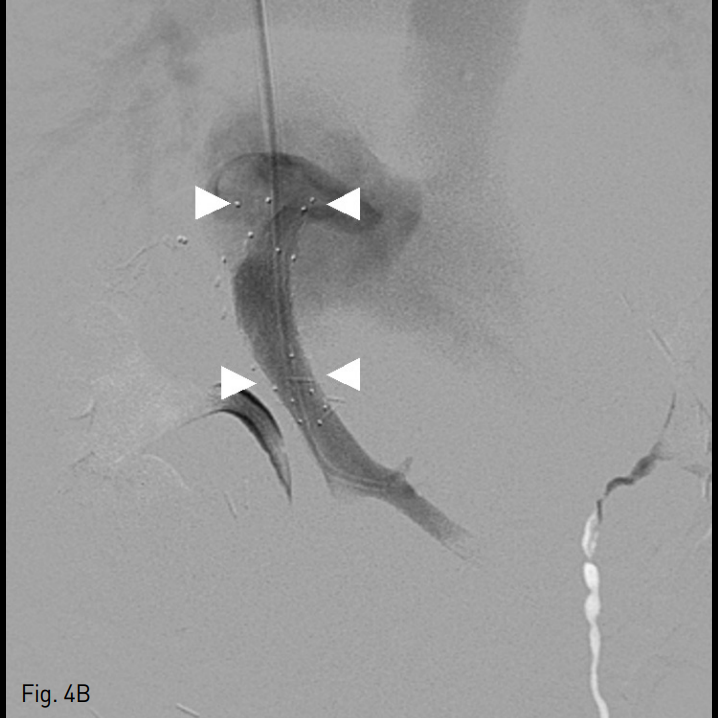

시술 후 환자의 컨디션과 혈액 검사 소견 호전되어 퇴원하였으나 시술 2주 후 다시 복부 팽만과 식이 섭취감소를 호소하며 내원하였다. 혈액 검사 소견 상 혈소판 수치 혈소판 수치 106,000/mm3, INR 1.82, albumin 3.4g/dL, total bilirubin 1.1mg/dL, AST 48U/L, ALT 49U/L로 첫 시술 전 보다는 정도가 낮으나 악화되어 있었다. 전산화 단층 촬영 상 간실질의 울혈을 시사하는 간실질의 불균질한 조영 증강이 관찰되었으며, 스텐트 내 충만결손 병변은 관찰되지 않았다(Fig. 3). 다시 환자의 내경정맥을 통해 5 Fr 혈관조영술용 카테터를 삽입하여 간정맥 내로 진입하였으며, 조영제 주입 시 혈류 정체와 함께 스텐트의 끝 주변으로 협착이 관찰되었으며 압력 차이는 19mmHg로 측정되었다 (Fig. 4A). 간정맥 협착 해소를 위해 14mm x 30mm 자가확장형 스텐트 (Zilver)를 삽입하고 8mm x 40mm 풍선 카테터 (Mustang)을 이용하여 혈관성형술을 시행하였다. 이후 시행한 간정맥 조영술 상 우심방으로의 혈류가 회복되었으며 압력 차이가 3mmHg로 줄어들었다 (Fig. 4B).

A. On contrast injection after catheter access to the hepatic vein via transjugular route, there was persistent stenosis at the anastomosis site (arrow) which is not covered by the previously inserted stent.

B. After additional stent inser tion (14mm x 30mm) and balloon angioplas ty (8mm x 40mm) at the anastomosis site the flow via the newly inserted stent (arrowheads: stent markers) to the right atrium restored, and the pressure gradient dropped from 19mmHg to 3mmHg.